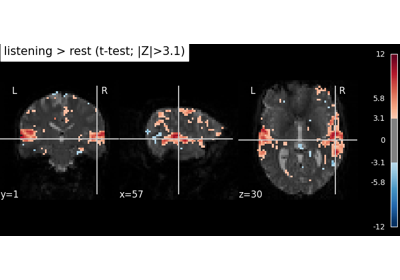

Examples using nilearn.datasets.fetch_spm_auditory¶

Intro to GLM Analysis: a single-run, single-subject fMRI dataset